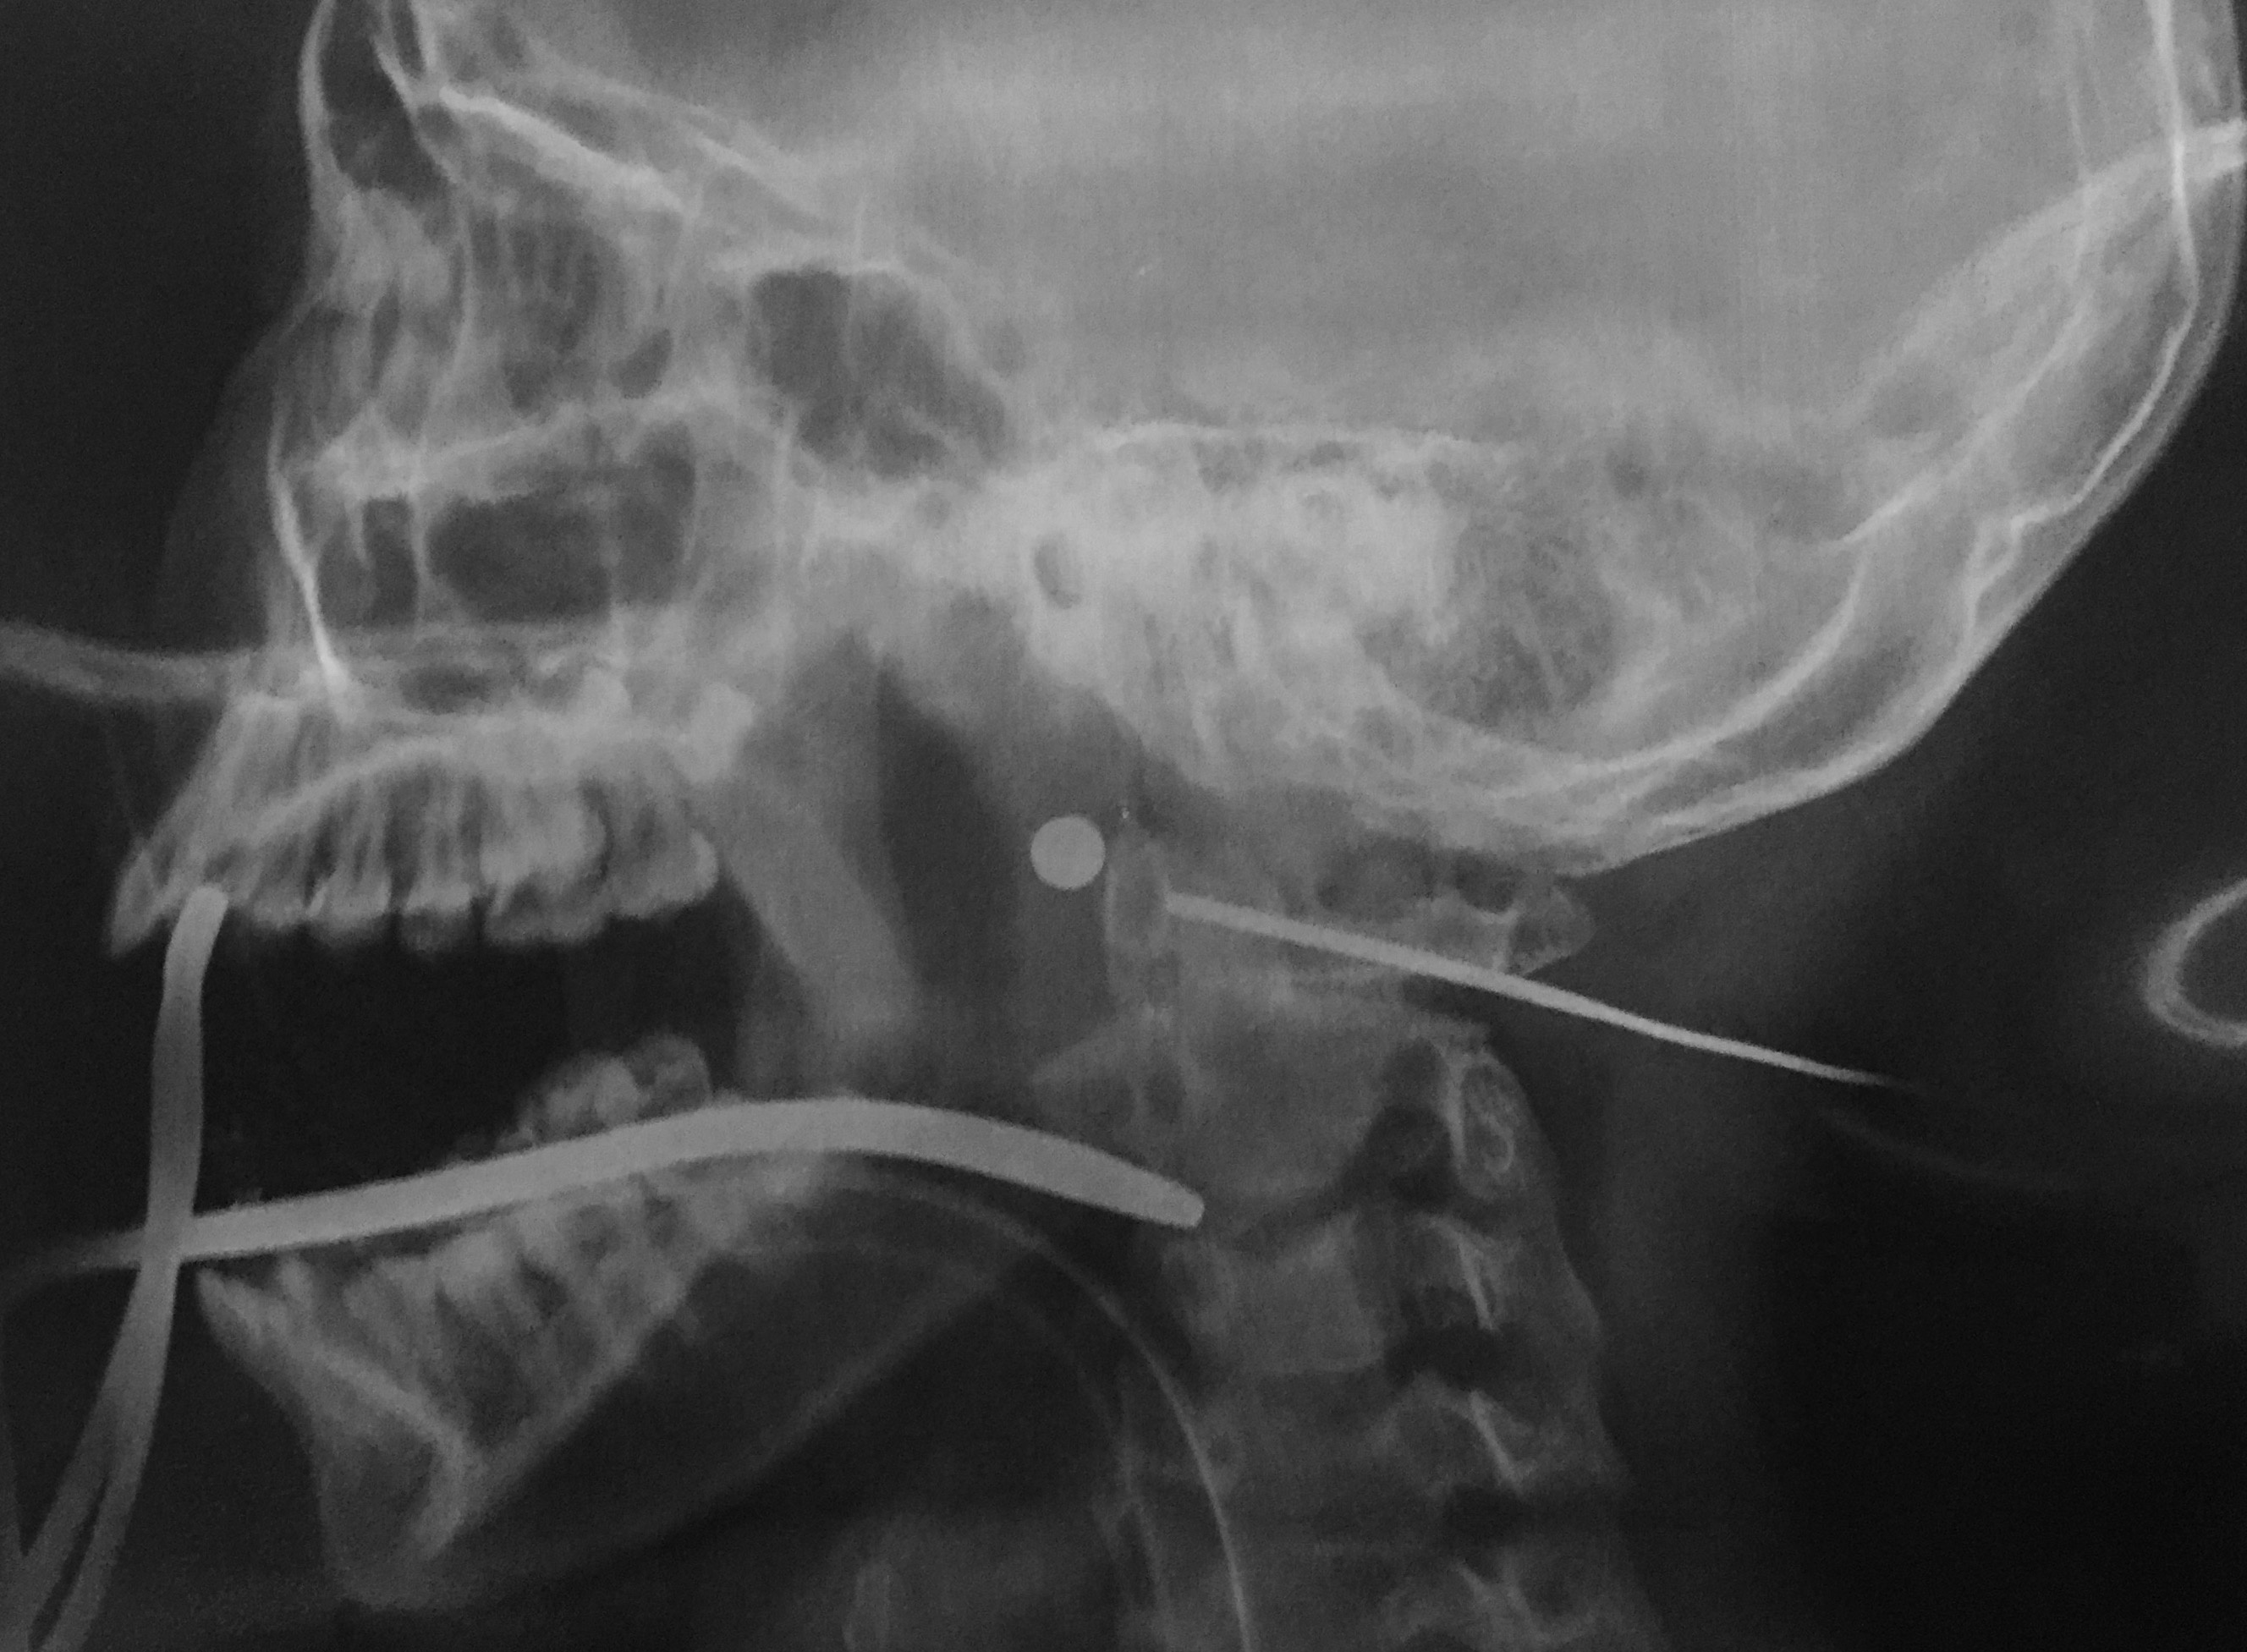

Nữ sinh 13 tuổi bị đạn bi bắn xuyên cổ

Đang ngồi xem tivi, Thảo nghe tiếng súng nổ. Sau đó bé thấy đau ở vùng tai rồi máu chảy rất nhiều. Các bác sĩ phẫu thuật lấy ra viên đạn bi trong cổ cháu gái.